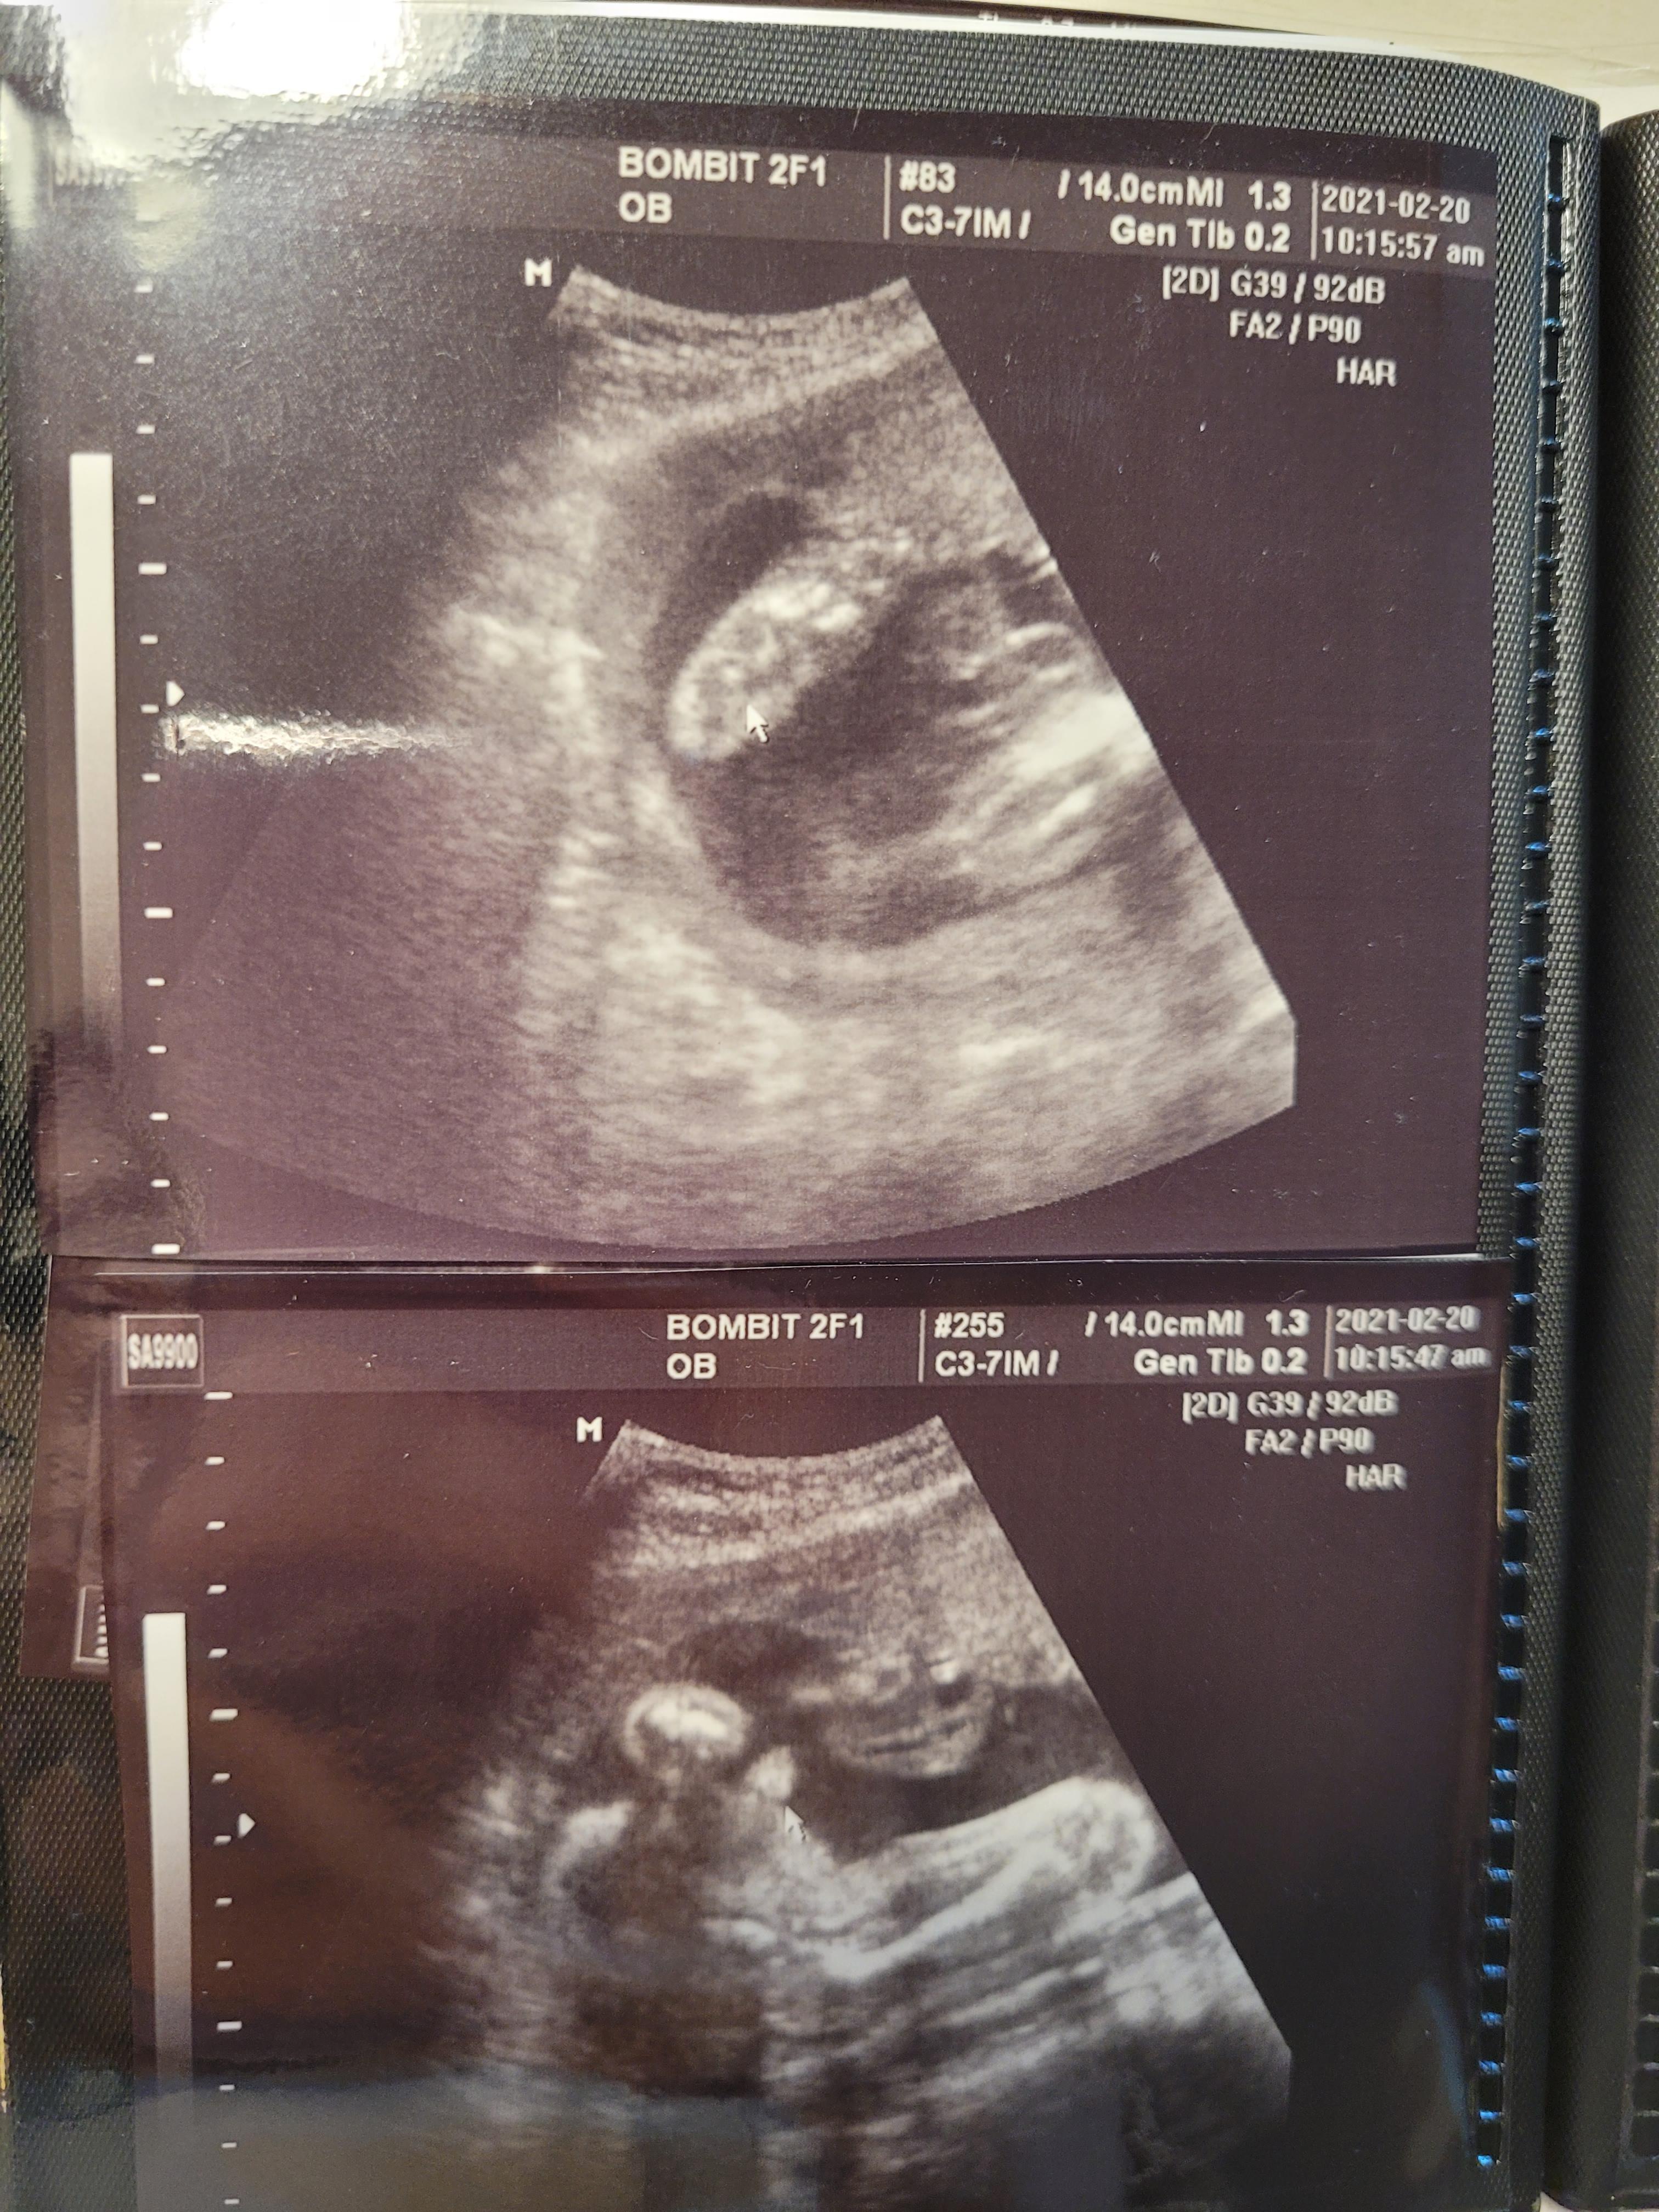

24주 초음파사진 / 24주 봄빛병원 정기검진

24주인데 2주나 앞서가는 우리 행복이..

머리둘레, 배둘레 다 체크하고 쑥쑥 잘 있는거 확인했어요.

아기는 900g정도되고, 양수도 넉넉하고 잘 있더라구요..^^